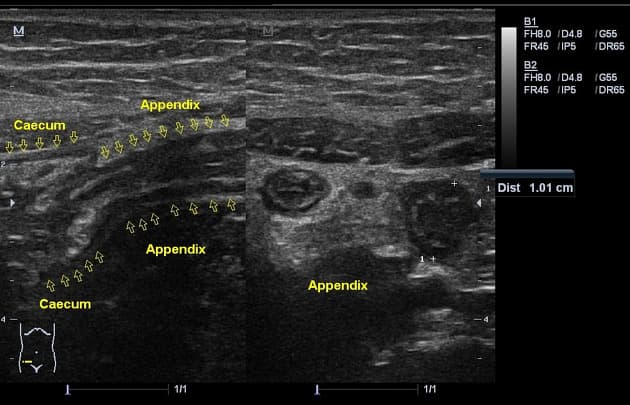

Acute appendicitis in pregnancy (MRI)

Thai 28 tuần, xuất hiện đau hạ sườn phải mới khởi phát.

Quan sát thấy một cấu trúc dạng ống giãn ở vùng hạ sườn phải, kèm tăng tín hiệu T2 xung quanh, gợi ý phù nề và viêm quanh cấu trúc này. Ngoài ra, ghi nhận một viên sỏi trong túi mật.

THẢO LUẬN: Đây là trường hợp viêm ruột thừa cấp ở bệnh nhân mang thai. Sau khi chụp MRI, bệnh nhân đã được phẫu thuật cắt ruột thừa mở, với theo dõi tim thai trước và sau phẫu thuật. Kết quả giải phẫu bệnh cho thấy: Ruột thừa to và giãn Thanh mạc màu xám sẫm đến nâu đỏ Có hiện tượng dính Dịch tiết nhầy mủ lan tỏa Lòng ruột thừa: Giãn Thành dày Các đặc điểm này phù hợp với chẩn đoán viêm ruột thừa cấp trên hình ảnh học. Bệnh nhân dung nạp phẫu thuật tốt, không có biến chứng và hồi phục thuận lợi. Ý nghĩa lâm sàng quan trọng: Trường hợp này nhấn mạnh rằng các bác sĩ lâm sàng và bác sĩ chẩn đoán hình ảnh cần luôn nghĩ đến viêm ruột thừa ở bệnh nhân mang thai có đau hạ sườn phải, vì: 👉 Tử cung mang thai có thể đẩy ruột thừa lên cao, làm thay đổi vị trí giải phẫu bình thường. Điều này có thể gây: Chẩn đoán chậm trễ Hoặc nhầm với bệnh lý gan mật Đồng tác giả: Amira Elfergani

Viêm ruột thừa cấp trong thai kỳ (chụp cộng hưởng từ)